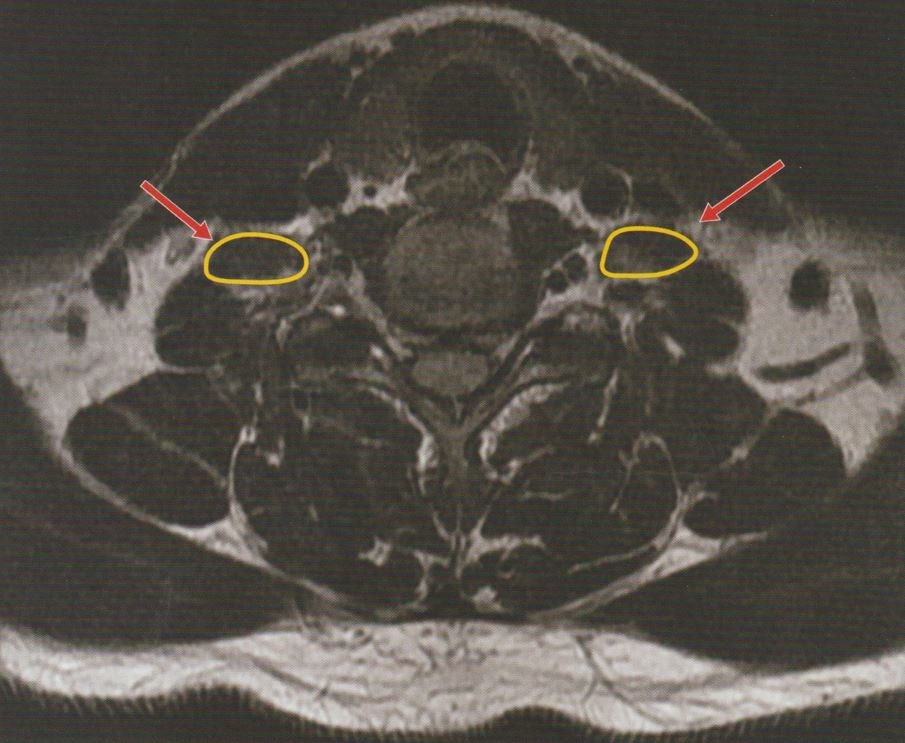

MRI 영상을 통해 확인할 수 있는 흉곽출구증후군 치료 시, 사각근에 적용하는 도침치료 포인트입니다.

사각근 위를 덮고 있는 흉쇄유돌근을 피해서 자침하면, 치료 효과를 더욱 높일 수 있습니다.

신경이 지나가는 부위에 대해 자침 깊이를 1cm 이내로 제한하여 진행하기 때문에, 안전하게 치료가 가능합니다.